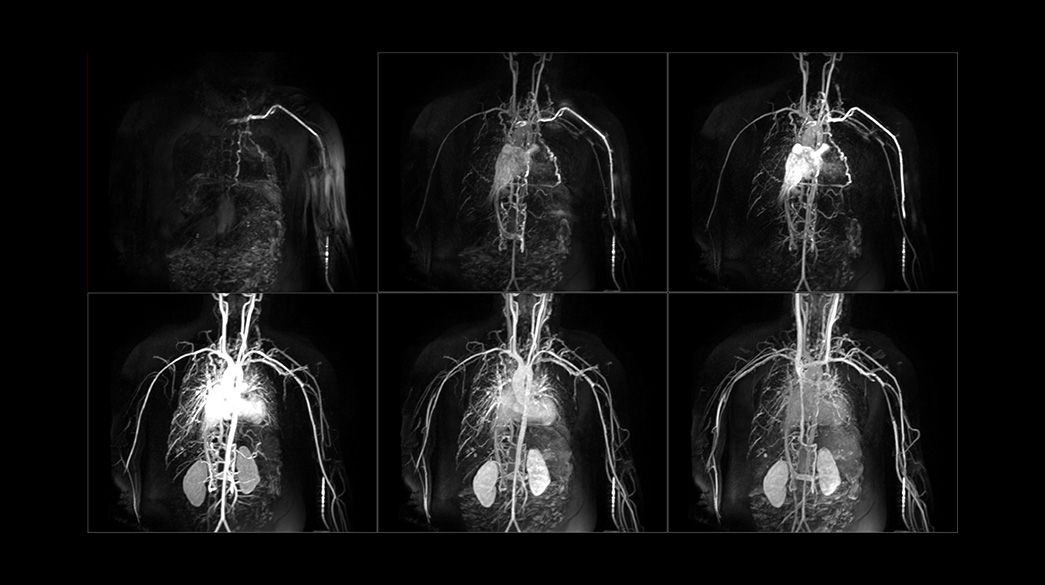

Fluoro Trigger MRA

Fluoroscopic triggering is a real-time bolus detection method of contrast arrival for vascular scans.

TRICKS

MR Angiography imaging that helps accelerate the temporal domain of 3D dynamic imaging – without compromising spatial resolution.

Inhance Suite

Improves workflow with easy setup through visualization of blood flow in diverse anatomies. Includes: 3D IFIR, 3D Velocity, 2D InFlow, 3D DeltaFlow